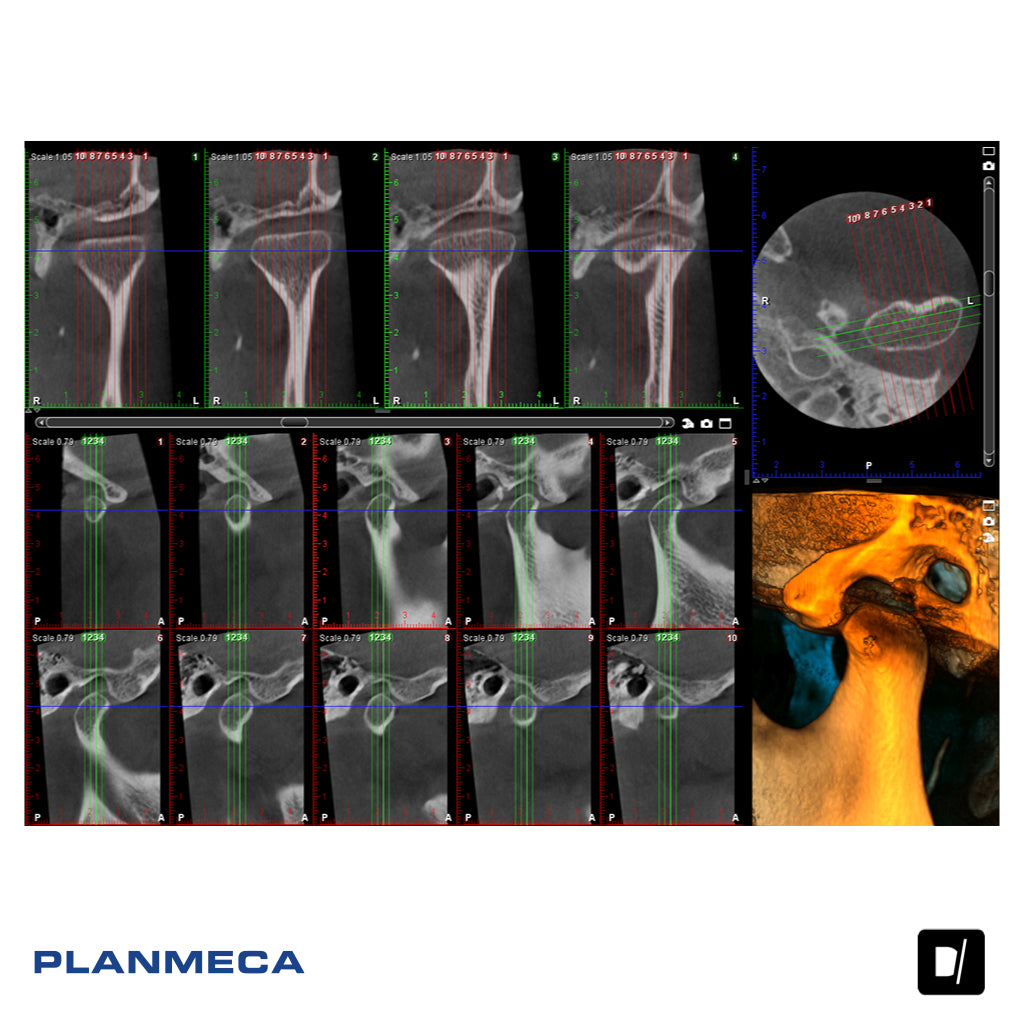

La familia de productos Planmeca Viso consta de tres fantásticas unidades de obtención de imágenes CBCT, todas ellas con una calidad de imagen excepcional para los profesionales de la odontología. La principal diferencia entre las unidades radica en los tamaños de volumen disponibles. Para Planmeca Viso® G7, los tamaños de volumen pueden ajustarse libremente entre 3 x 3 y 30 x 30, mientras que Planmeca Viso® G5 admite tamaños de volumen de 3 x 3 a 20 x 17 cm y Planmeca Viso® G3 de 3 x 3 a 20 x 10 cm.

Posicionamiento en directo del FOV virtual

El posicionamiento del paciente se realiza directamente desde el panel de control de la unidad utilizando cámaras integradas y una vista en directo del paciente, que permite ver al paciente en directo desde el panel de control para un posicionamiento flexible y exacto del FOV. El tamaño de volumen también puede ajustarse libremente.

Imágenes dentales versátiles

Planmeca Viso ofrece una amplia selección de volúmenes para cubrir todas las necesidades clínicas, desde un solo diente hasta un cráneo completo. El sensor de las unidades 3D también es plenamente capaz de obtener imágenes 2D.